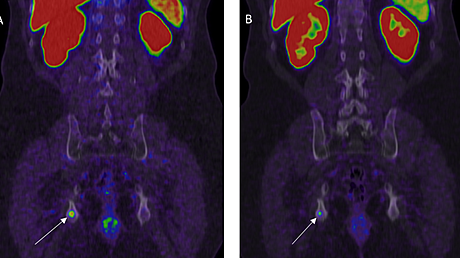

A 77-year-old female presented to our outpatient department with a history of coccydynia for the past three months. The patient was initially thought of a simple coccydynia and was started on conservative treatment for coccydynia. However, the patient's symptoms were not relived and she complained of increasing pain which was present during the night also. On physical examination, an ill-defined mass of 10 x 8 cm approximately, hard in consistency was noticed in the coccygeal region. The mass was found to be fixed to the underlying structures and immobile. On per rectal examination, the mass could be felt in the left posterior quadrant which was hard in consistency and surface was found to be lobulated. The patient had no history of constitutional symptoms. Plain X-ray of the pelvis showed an ill-defined shadow of the mass with a corresponding destruction of the coccyx. Contrast computed tomography (CT) of abdomen and pelvis revealed a heterogenous lesion of soft tissue density in the midline and left paramedian region of the coccyx (extending into pre- and postcoccygeal plane) measuring 8.4 x 8.9 cm as seen in Figure 1.

Based on the appearance and location, the differential diagnosis included chordoma or a soft tissue sarcoma. The chest radiograph was normal. Biopsy was done, which showed diagnosis to be sclerosing epithelioid sarcoma. Positron emission tomography (PET) scan was done which showed no metastasis.